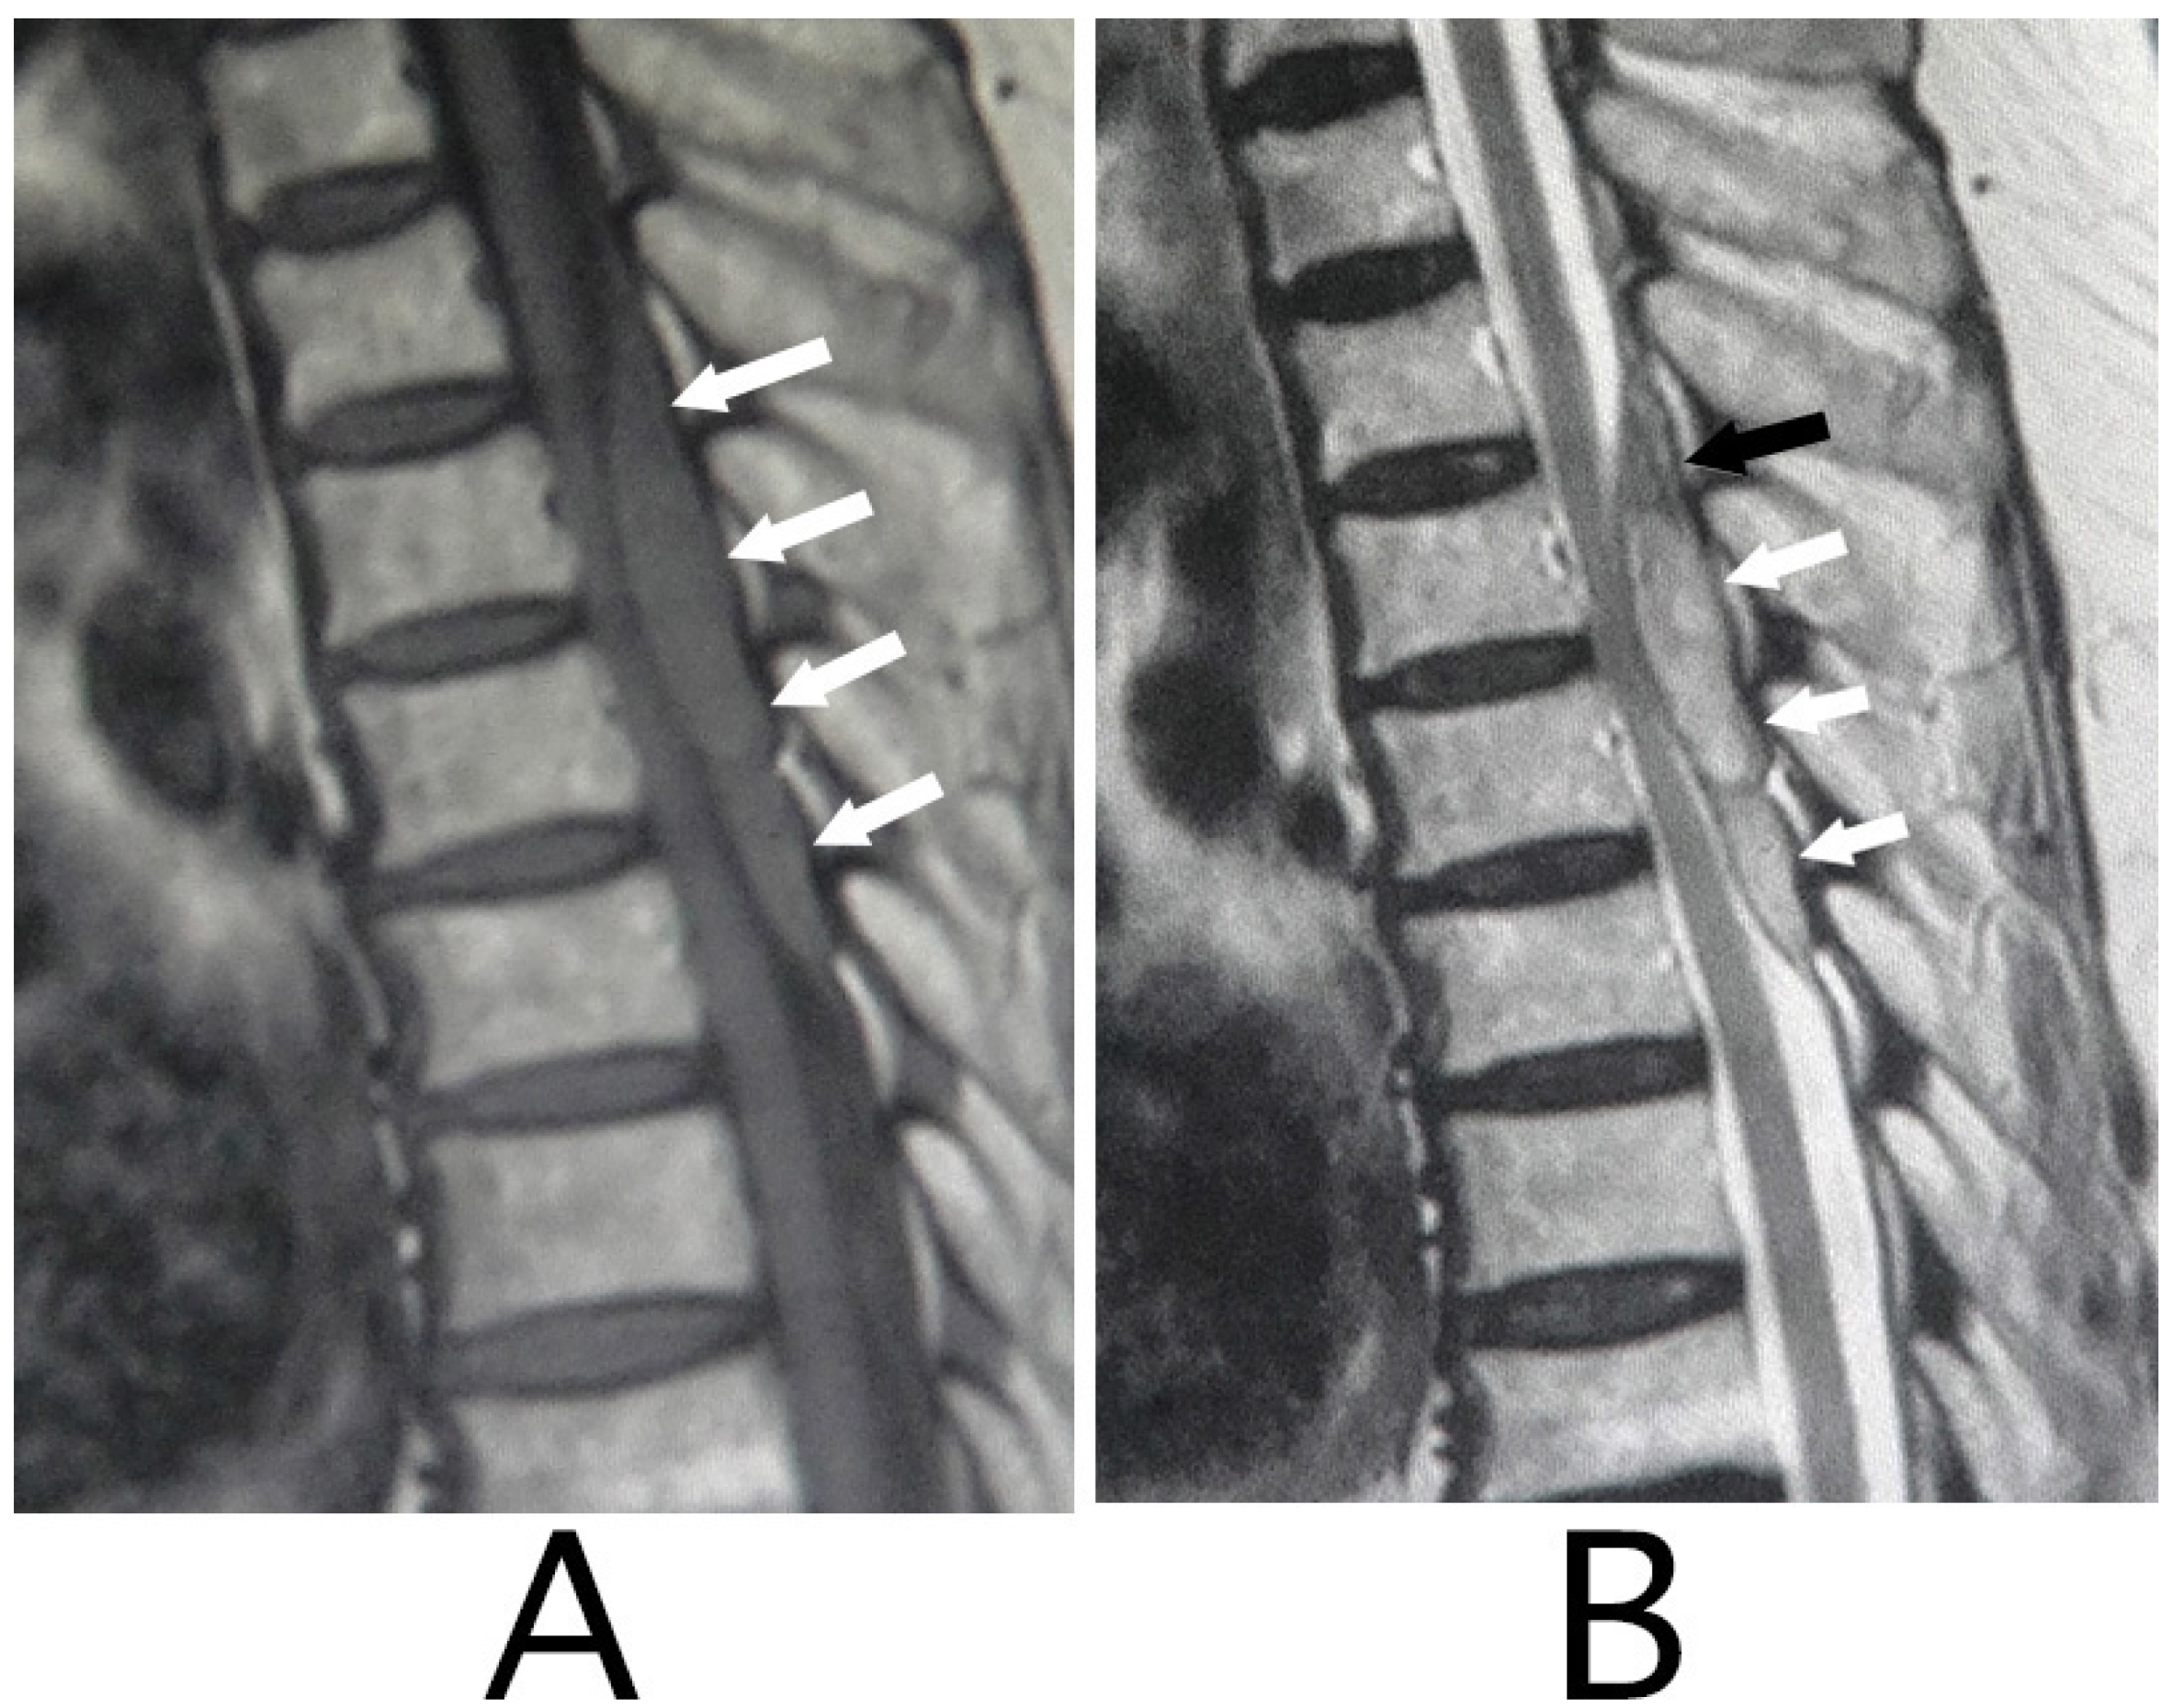

MRI of the spinal cord analysis was performed because the presence of acute lesions on the spinal cord was suspected, based on neurological findings and the clinical course. As a result, sagittal T1-weighted MRI showed an iso-intensity mass in the epidural space behind the spinal cord at the level from Th3 to Th6 (Figure 1A). Compression of the spinal cord was shown at the level between Th4 and Th6 (Figure 1A,B). The lesion was delineated as a high-intensity mass with heterogeneity and a superiorly adhered iso-intensity region in sagittal T1-weighted images (Figure 1B). Axial T1-weighted MRI showed an iso-intensity mass in the posterior part of the epidural space and a deviation of the spinal cord to the anterior direction (Figure 2A). The lesion was delineated as a heterogeneous high-intensity mass in axial T2-weighted MRI images (Figure 2B).

Figure 1. Sagittal MRI. An iso-intensity mass in the epidural space was shown behind the spinal cord at the level from Th3 to Th6 (white arrows) (T1-weighted image; (A)). The lesion was observed as a heterogeneous high-intensity mass (white arrows) and a superiorly adhered iso-intensity region (T2-weighted image; a black arrow) (B).